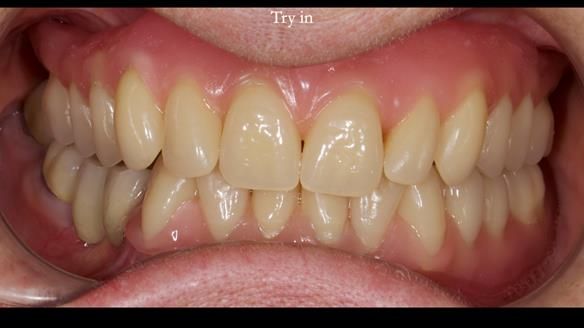

Mary’s upper occlusal plane wasn’t parallel to her interpupillary line, and she specifically wanted that natural asymmetry preserved. Rowan arranged the teeth beautifully, following the exact contour and character of her original smile.

For both the upper and lower dentures, we used Schottlander Enigma Life teeth. I’ve been using these since 2014 and they’ve been outstanding - the surface texture, colour depth, and light reflection are superb. When arranged to mirror the patient’s natural tooth positions, they look completely lifelike.

- Enigma Life teeth provided a natural, individualised appearance perfectly matching Mary’s desired smile.